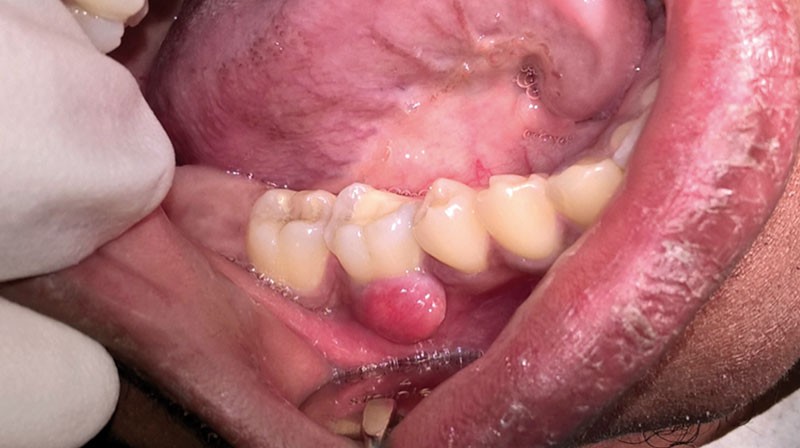

Lorsqu’un patient se présente en consultation avec une lésion au contact d’une dent (fig. 2), le praticien doit suivre une démarche diagnostique afin de recueillir le maximum d’informations sur la situation clinique :